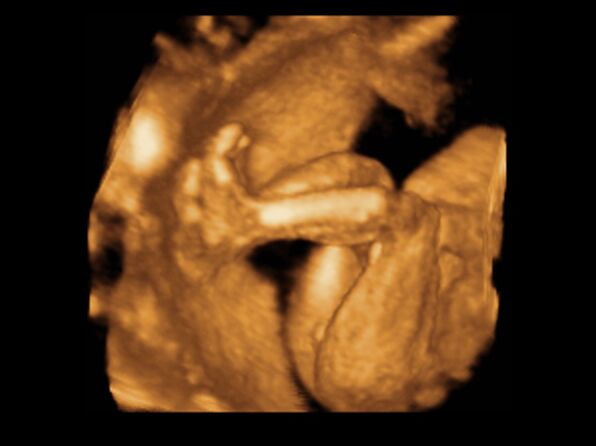

Huhh, hát annyira jó élmény volt, most tök boldog vagyok! Nagyon örülök, hogy mégis elmentem mégegyszer, mert sokat vacilláltam ám. A 4D Genesis egyszerűen szuper, mindenkinek nagyon nagyon tudom ajánlani, ezen belül is engem a Lengyel Györgyné Márti fogadott. Szuper ez a nő, akkora átéléssel és profizmussal csinálta az egész vizsgálatot! Mindent részletesen megnézett, megmutatott, elmagyarázott, nem sajnálta az időt. A felvétel gyönyörű lett, az egész baby nagyon szépen látszik, végig fent volt és mocorgott, hihetetlen aranyos volt, és nagyon szép!

Bemutatott párszor, ezek mind meg is vannak örökítve!

Na és a lényeg...jöjjenek a sztárfotók! Bocsi előre, 8 lesz és kicsit nagyok, de nem tudtam választani, azokat a bemutatásokat mind muszáj volt felraknom, tök vicces!